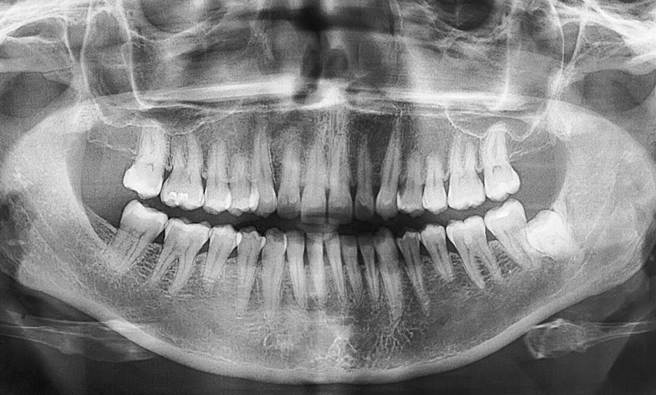

正常青少年约有20颗牙齿,成人加上智齿则有32颗。印度一名7岁男童因为牙痛就医,竟发现他的口腔内藏有526颗牙齿,是一般成人的26倍,也比拥有300颗牙齿的大白鲨还多,因此被医护称作「大白鲨男孩」,所幸医疗团队透过拔牙手术,成功拔除多余的牙齿,目前男童的牙齿数量已恢復正常。

根据《每日星报》报导,2019年一名年仅7岁的印度男童拉文德兰(Ravindran),被发现口腔内长满密密麻麻的牙齿,让医护人员全都吓一大跳。新闻曝光后,印度钦奈牙科学院愿意出手帮助男童,替他进行拔牙手术,耗费数小时拔出共526颗牙齿,比拥有300颗牙齿的大白鲨还要多,如今拉文德兰只剩下21颗牙齿。

牙医罗曼尼(Pratibha Ramani)表示,拉文德兰的数百颗牙齿并不是全长在牙龈上,大部分都藏在口中一颗肉囊内长达4年,且牙齿的尺寸各异,从0.1毫米到3毫米都有,大的比一般牙齿还大,小的又只有米粒般大小。

然而儘管拉文德兰有着异于常人的牙齿数量,却没有觉得很痛苦,唯一的困扰就是其中一侧的牙齿没有长出来,偶尔会感到疼痛;除此之外,牙医诊断他患有「复合性牙瘤(compound composite odontoma)」,但仍不清楚形成的原因。